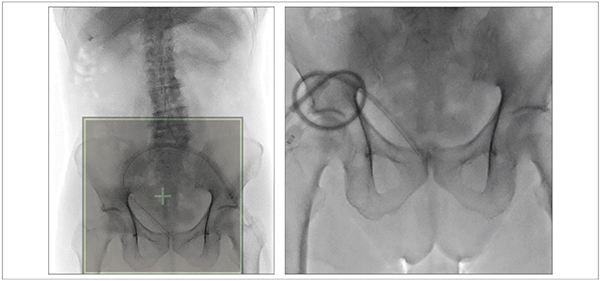

図8は、右腎瘻のカテーテル交換症例である。全体像(図8 a)から患者を移動することなく、右腎の一部を拡大し、カテーテル交換を行った(図8 b)。i-fluoro使用下での造影剤内のワイヤーやカテーテルの視認性も十分であった。図9は膀胱瘻造影症例で、i-fluoroを用いて骨盤部の拡大を行ったが、本症例も同様に必要な情報がきれいに視認できた。当院では、骨盤内の子宮卵管造影も行っているが、一度患者が天板に乗ると患者の移動が困難な検査の一つとして、i-fluoroの有用性を産婦人科とともに評価している。

図9 i-fluoroの使用例:膀胱瘻造影症例

(パルスレート:7.5fps、線量モード:Normal)